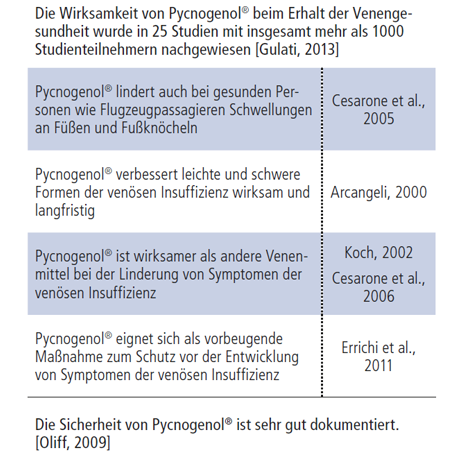

Es wurde sowohl in präklinischen als auch in klinischen Studien gezeigt, dass Pycnogenol® die Kapillarwände stärkt und Ödeme verhindert. Forschungsarbeiten haben gezeigt, dass Pycnogenol® sogar die brüchigen Kapillaren versiegelt und das Ausströmen von Flüssigkeit und Blut ins Gewebe, das zu Schwellungen, Ödemen und Mikroblutungen führt, stoppt. In Verbindung mit seinen entzündungshemmenden Eigenschaften und der patentierten Verringerung der Thrombozytenaggregation sind dies die grundlegenden Wirkmechanismen für gesunde Venen mit Pycnogenol®.

In einigen Fällen können allgemeine Schwellungen der Beine sich zu einer gefährlichen chronisch-venösen Insuffizienz (CVI) entwickeln, die, wenn sie nicht behandelt wird, zu Komplikationen und Ulzerationen (Geschwürbildungen) führen kann. Bisher wurden 15 klinische Studien mit insgesamt 784 Patienten zu venöser Insuffizienz und Pycnogenol® veröffentlicht. Die hohe Wirksamkeit von Pycnogenol® als Therapie der venösen Insuffizienz war in der Tat in zahlreichen Studien so deutlich, dass es regelmäßig zusammen mit bekannten Arzneimitteln für gesunde Venen untersucht wird. Dies wird in einer deutschen Doppelblind-Vergleichsstudie mit 40 CVI-Patienten deutlich. Es wurde gezeigt, dass Pycnogenol® in einer geringeren Dosierung Ödeme der unteren Extremitäten wirksamer verringerte und die Symptome der CVI wirksamer linderte als Rosskastaniensamenextrakt. Darüber hinaus untersuchte eine klinische Studie mit 70 Patienten die Wirkung von Pycnogenol® bei der Behandlung der venösen Insuffizienz im Vergleich zu Troxerutin, einem wasserlöslichen Derivat von Rutin, einer üblichen Behandlung für die CVI. Nach einer Behandlung über 60 Tage erzielte eine Kombination aus Troxerutin und Pycnogenol® signifikantere Ergebnisse bei der Linderung der Symptome der CVI als Troxerutin alleine.

Wenn wir durch überfüllte Flughäfen eilen, müssen wir besonders darauf achten, gesund zu bleiben. Beim Reisen ist es wichtig, an die Gesundheit unserer Venen zu denken. Lange Zeiträume ohne Bewegung, eine verminderte Flüssigkeitsaufnahme und der Wasserverlust bei trockenem, niedrigem Kabinendruck tragen aufgrund unzureichender Blutzirkulation zu Schwellungen bei, wobei sich im gesamten Beingewebe Flüssigkeit staut. Die meisten Menschen bemerken die Auswirkungen der Schwellungen während einesFlugs, wenn sie ihre Schuhe ausgezogen haben und dann Schwierigkeiten haben, sie am Ende des Flugs wieder anzuziehen. Geschwollene Beine und Fußknöchel können zu gefährlichen Komplikationen wie Venenthrombosen führen. Eine der jüngsten klinischen Studien fand heraus, dass Pycnogenol® eine positive Auswirkung auf das Anschwellen der Beine (Ödem) während Langstreckenflügen zwischen 7 und 12 Stunden haben kann. In einer in "Clinical and Applied Thrombosis/Hemostasis" veröffentlichten Arbeit untersuchten Forscher die Anschwellung der Fußknöchel von 169 Teilnehmern während eines Fluges. Es wurde festgestellt, dass die Passagiere, die Pycnogenol® einnahmen, weniger Schwellungen und Schmerzen in den Beinen und Fußknöcheln hatten. Beide Symptome sind häufig mit Langstreckenreisen verbunden.

Zu den weiteren bemerkenswerten Forschungsarbeiten gehört eine Studie mit 211 Passagieren auf einem Langstreckenflug (7-12 Stunden), die Pycnogenols Wirksamkeit bei der Vorbeugung von Thrombosen zeigte. Die Passagiere nahmen zwei 100mg-Kapseln Pycnogenol® zwei bis drei Stunden vor dem Abflug und weitere zwei Kapseln nach sechs Stunden während des Flugs ein. Eine weitere Kapsel wurde am nächsten Tag nach der Ankunft eingenommen. Während in der Placebo Kontrollgruppe fünf Fälle von (transienten) Thrombosen auftraten, entwickelte keiner der Passagiere, die Pycnogenol® einnahmen, während des Flugs eine Thrombose.